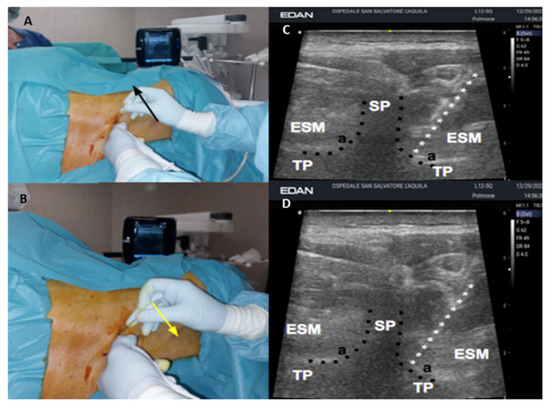

2. Case Presentation